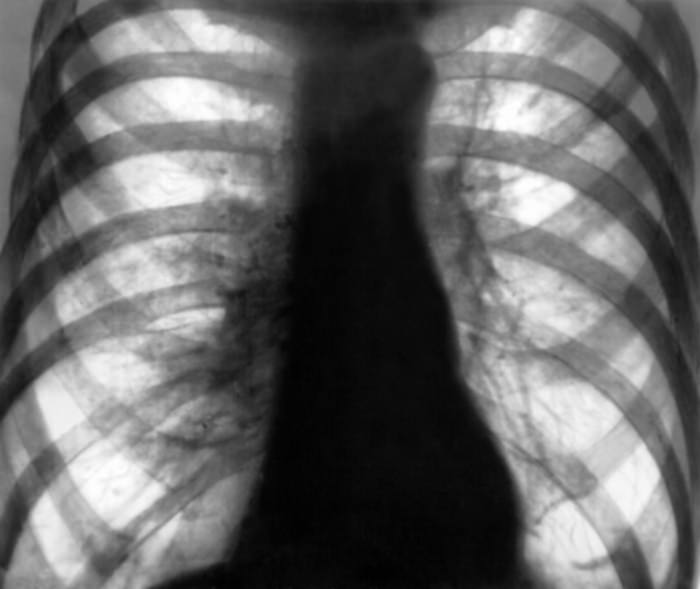

При вторичной эмфиземе происходят серьезные нарушения газового состава крови. Также при обоих видах эмфиземы уменьшаются дыхательные экскурсии, грудная клетка становится бочкообразной. Надключичные области выбухают, появляется перкуторный звук, уменьшается подвижность диафрагмы и ее расположение. На рентгенограмме видна повышенная прозрачность легочных полей.

В историях болезни можно обнаружить интересные рентгеновские снимки, наглядно демонстрирующие патологическую картину эмфиземы легких. Отчетливо видны буллы при буллезной форме — в виде светлых округлых полостей. Обеднение сосудистого рисунка, уплощение диафрагмы, прозрачные легочные поля типичны для диффузных форм эмфиземы.